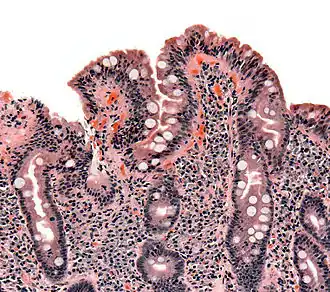

![]() Биопсия тонкого кишечника больного целиакией. Видна уплощенная форма ворсинок, лейкоцитарная инфильтрация и гиперплазия крипт. | |